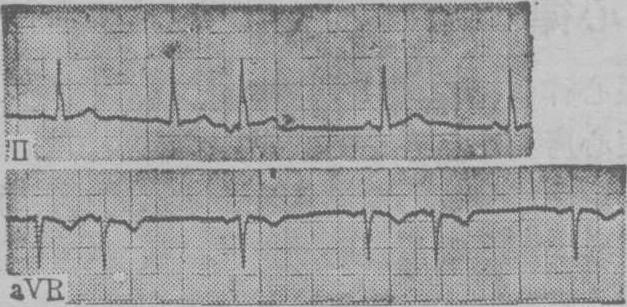

图1 房室交接处性早搏

图示上行第3和下行第2、第5个心搏有提前出现的逆行P′波,在Ⅱ中倒置,在aVR呈直立,P′-R间期为0.1 s,QRS波群形态与窦性的相同,早搏后代偿间歇不完全。